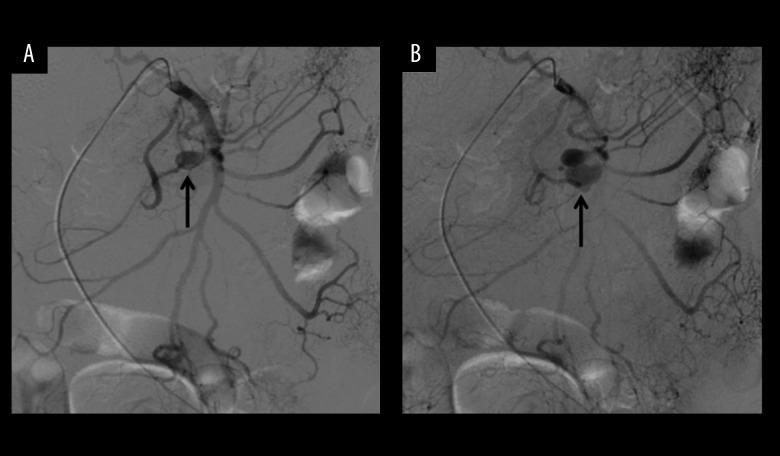

We encountered a rare case of a ruptured pancreaticoduodenal artery aneurysm with an atypical clinical presentation that simulated acute pancreatitis. A 71-year-old woman was admitted to the emergency department with abdominal pain in the left upper quadrant, a slightly elevated level of pancreatic amylase, and cholelithiasis on ultrasonography. With persistent pain and progressively decreasing hemoglobin level, computed tomography with contrast showed fluid collection in the subphrenic space, a retroperitoneal hematoma, and a pancreaticoduodenal artery aneurysm that appeared to originate from a branch of the SMA. Urgent angiography indicated spontaneous rupture of a pancreaticoduodenal artery aneurysm. Emergent surgery was undertaken, and a simple aneurysmectomy was successfully performed. The patient's recovery was unremarkable. The prompt diagnosis of a pancreaticoduodenal artery aneurysm was difficult because the initial symptoms were vague and misleading in our case.

我们遇到了一例罕见的胰十二指肠动脉破裂性动脉瘤,其临床表现不典型,类似急性胰腺炎。一名71岁女性因左上腹疼痛、胰淀粉酶水平轻度升高且超声检查发现胆结石而入住急诊科。由于疼痛持续且血红蛋白水平逐渐下降,增强计算机断层扫描显示膈下间隙有积液、腹膜后血肿以及一个似乎起源于肠系膜上动脉分支的胰十二指肠动脉动脉瘤。紧急血管造影显示胰十二指肠动脉动脉瘤自发破裂。进行了急诊手术,并成功实施了单纯动脉瘤切除术。患者恢复情况良好。在我们的病例中,由于初始症状模糊且具有误导性,所以难以迅速诊断出胰十二指肠动脉动脉瘤。